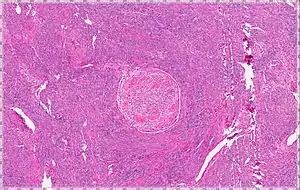

| Intravenous Leiomyoma |